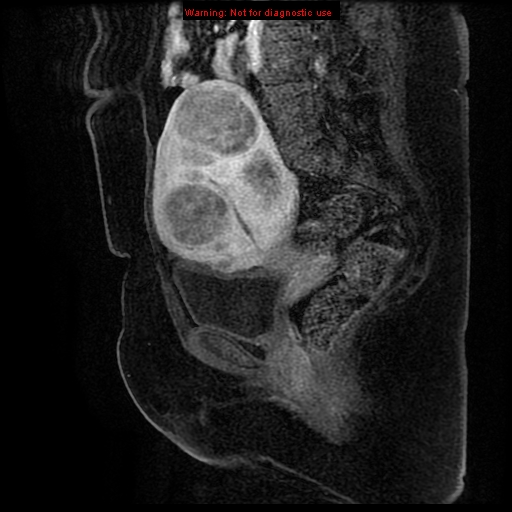

MRI

• US in 2 weeks to assess the uterine size